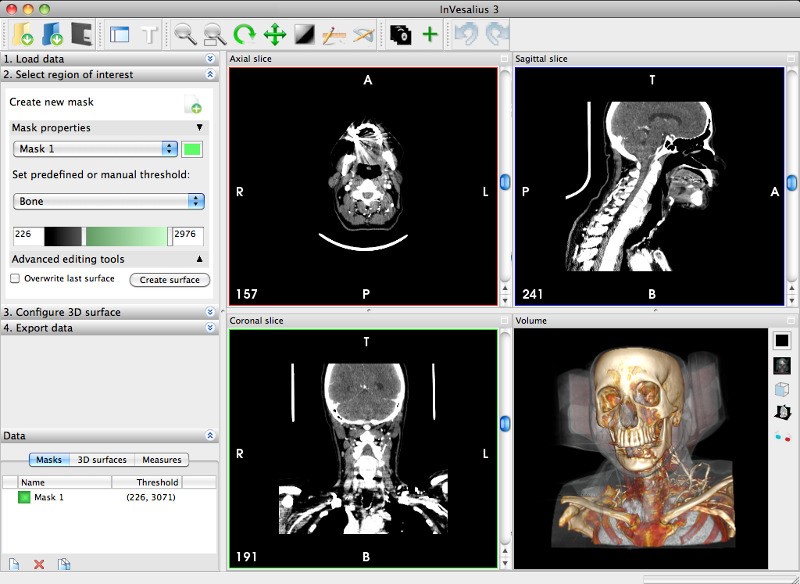

Лазерная камера для печати медицинских изображений на пленке стандарт dicom